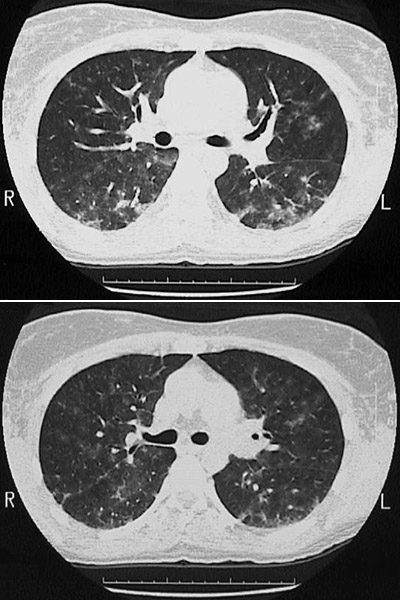

The chest CT scan views in "lung window" seen here demonstrate nodular ground glass opacifications in a patient with hypersensitivity pneumonitis.